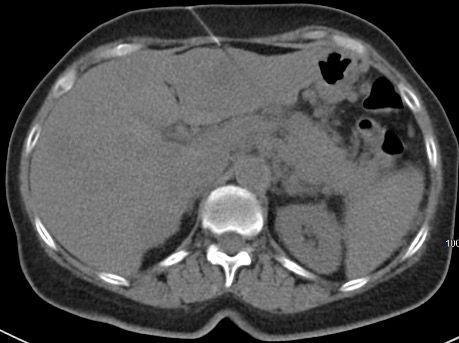

A White woman aged 62 years noted poor appetite, occasional nausea, vomiting, indigestion, and a 30-pound weight loss starting 6 months prior to her diagnosis. Initial evaluation, including upper and lower endoscopies, revealed Barretts esophagus with no dysplasia, a cecal polyp, and negative celiac disease markers. Treatment with proton pump inhibitors did not help her symptoms. As time passed, she noted occasional epigastric and right upper quadrant abdominal pain. Further evaluation with ultrasound and a CT scan of the abdomen revealed a large necrotic mass in the pancreatic body/tail extending to the splenic hilum with invasion into the spleen, as well as multiple enhancing lesions throughout the liver(Figure 1A). A CT-guided biopsy of a liver lesion revealed a metastatic, well-differentiated, high-grade (grade 3) NET with rosette formation, high mitotic rate (more than 20 per high power field), and a Ki-67 index of 30% (Figure 2 A,B). Further work-up with 68gallium 68-dotatate PET-CT confirmed a large pancreatic body/tail PET avid mass with direct extension involving the splenic hilum and multiple hepatic metastases. (Figure 1B). Ultrasound of the thyroid and parathyroid glands andMRI of the brain was negative. Serum gastrin, glucagon, and vasoactive intestinal peptide levels were normal. She had no fasting or nocturnal hypoglycemia. Serum chromogranin A level was elevated at 754 ng/mL (normal 0-103). A genetic consultation and work-up by our certified genetic counselor did not reveal any familial neuroendocrine syndrome.

Figure 1A. Large necrotic mass in the pancreatic body/tail extending to the splenic hilum with the invasion into spleen. Multiple enhancing lesions throughout the liver.